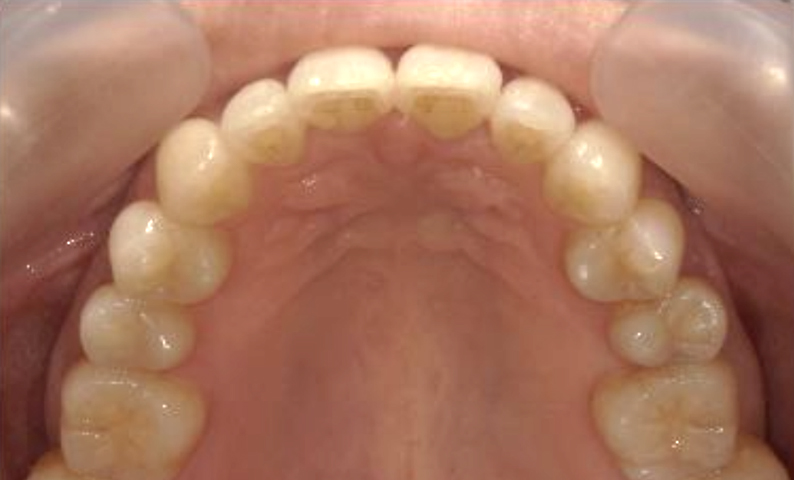

症例_002 下顎だけの部分矯正

治療期間:6ヶ月金額:21万円+税女性前歯のデコボコ下の前歯だけ

| Before | After |